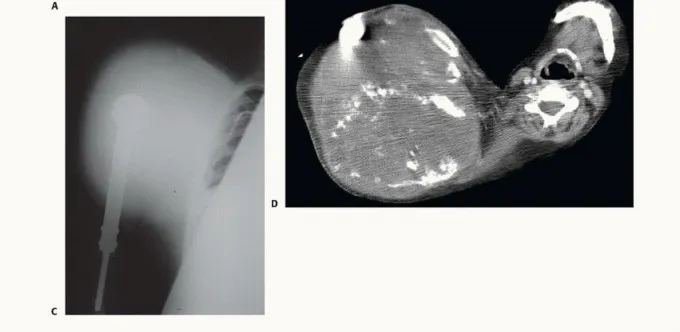

السبب الأكثر شيوعاً لبتر الربع الأمامي هو وجود أورام خبيثة عدوانية في العظام أو الأنسجة الرخوة في منطقة الكتف، والتي لا يمكن استئصالها مع الحفاظ على طرف وظيفي. من أمثلة هذه الأورام:

* الساركوما العظمية (Osteosarcoma): سرطان يصيب العظام بشكل مباشر.

* الساركوما الغضروفية (Chondrosarcoma): سرطان ينشأ في الخلايا الغضروفية.

* ساركوما إيوينغ (Ewing Sarcoma): نوع نادر وشرس من سرطانات العظام يصيب عادة الأطفال والشباب.

إذا غزا الورم الضفيرة العضدية أو الأوعية الدموية الرئيسية تحت الترقوة، يصبح إنقاذ الطرف مستحيلاً، ويكون البتر هو السبيل الوحيد لمنع انتشار السرطان (Metastasis) إلى الرئتين أو الدماغ.

- التصوير الطبي المتقدم: استخدام التصوير بالرنين المغناطيسي (MRI)، والتصوير المقطعي المحوسب (CT Scan)، والتصوير المقطعي بالإصدار البوزيتروني (PET Scan) لرسم خريطة دقيقة للورم وتأكيد عدم انتشاره لأعضاء أخرى.